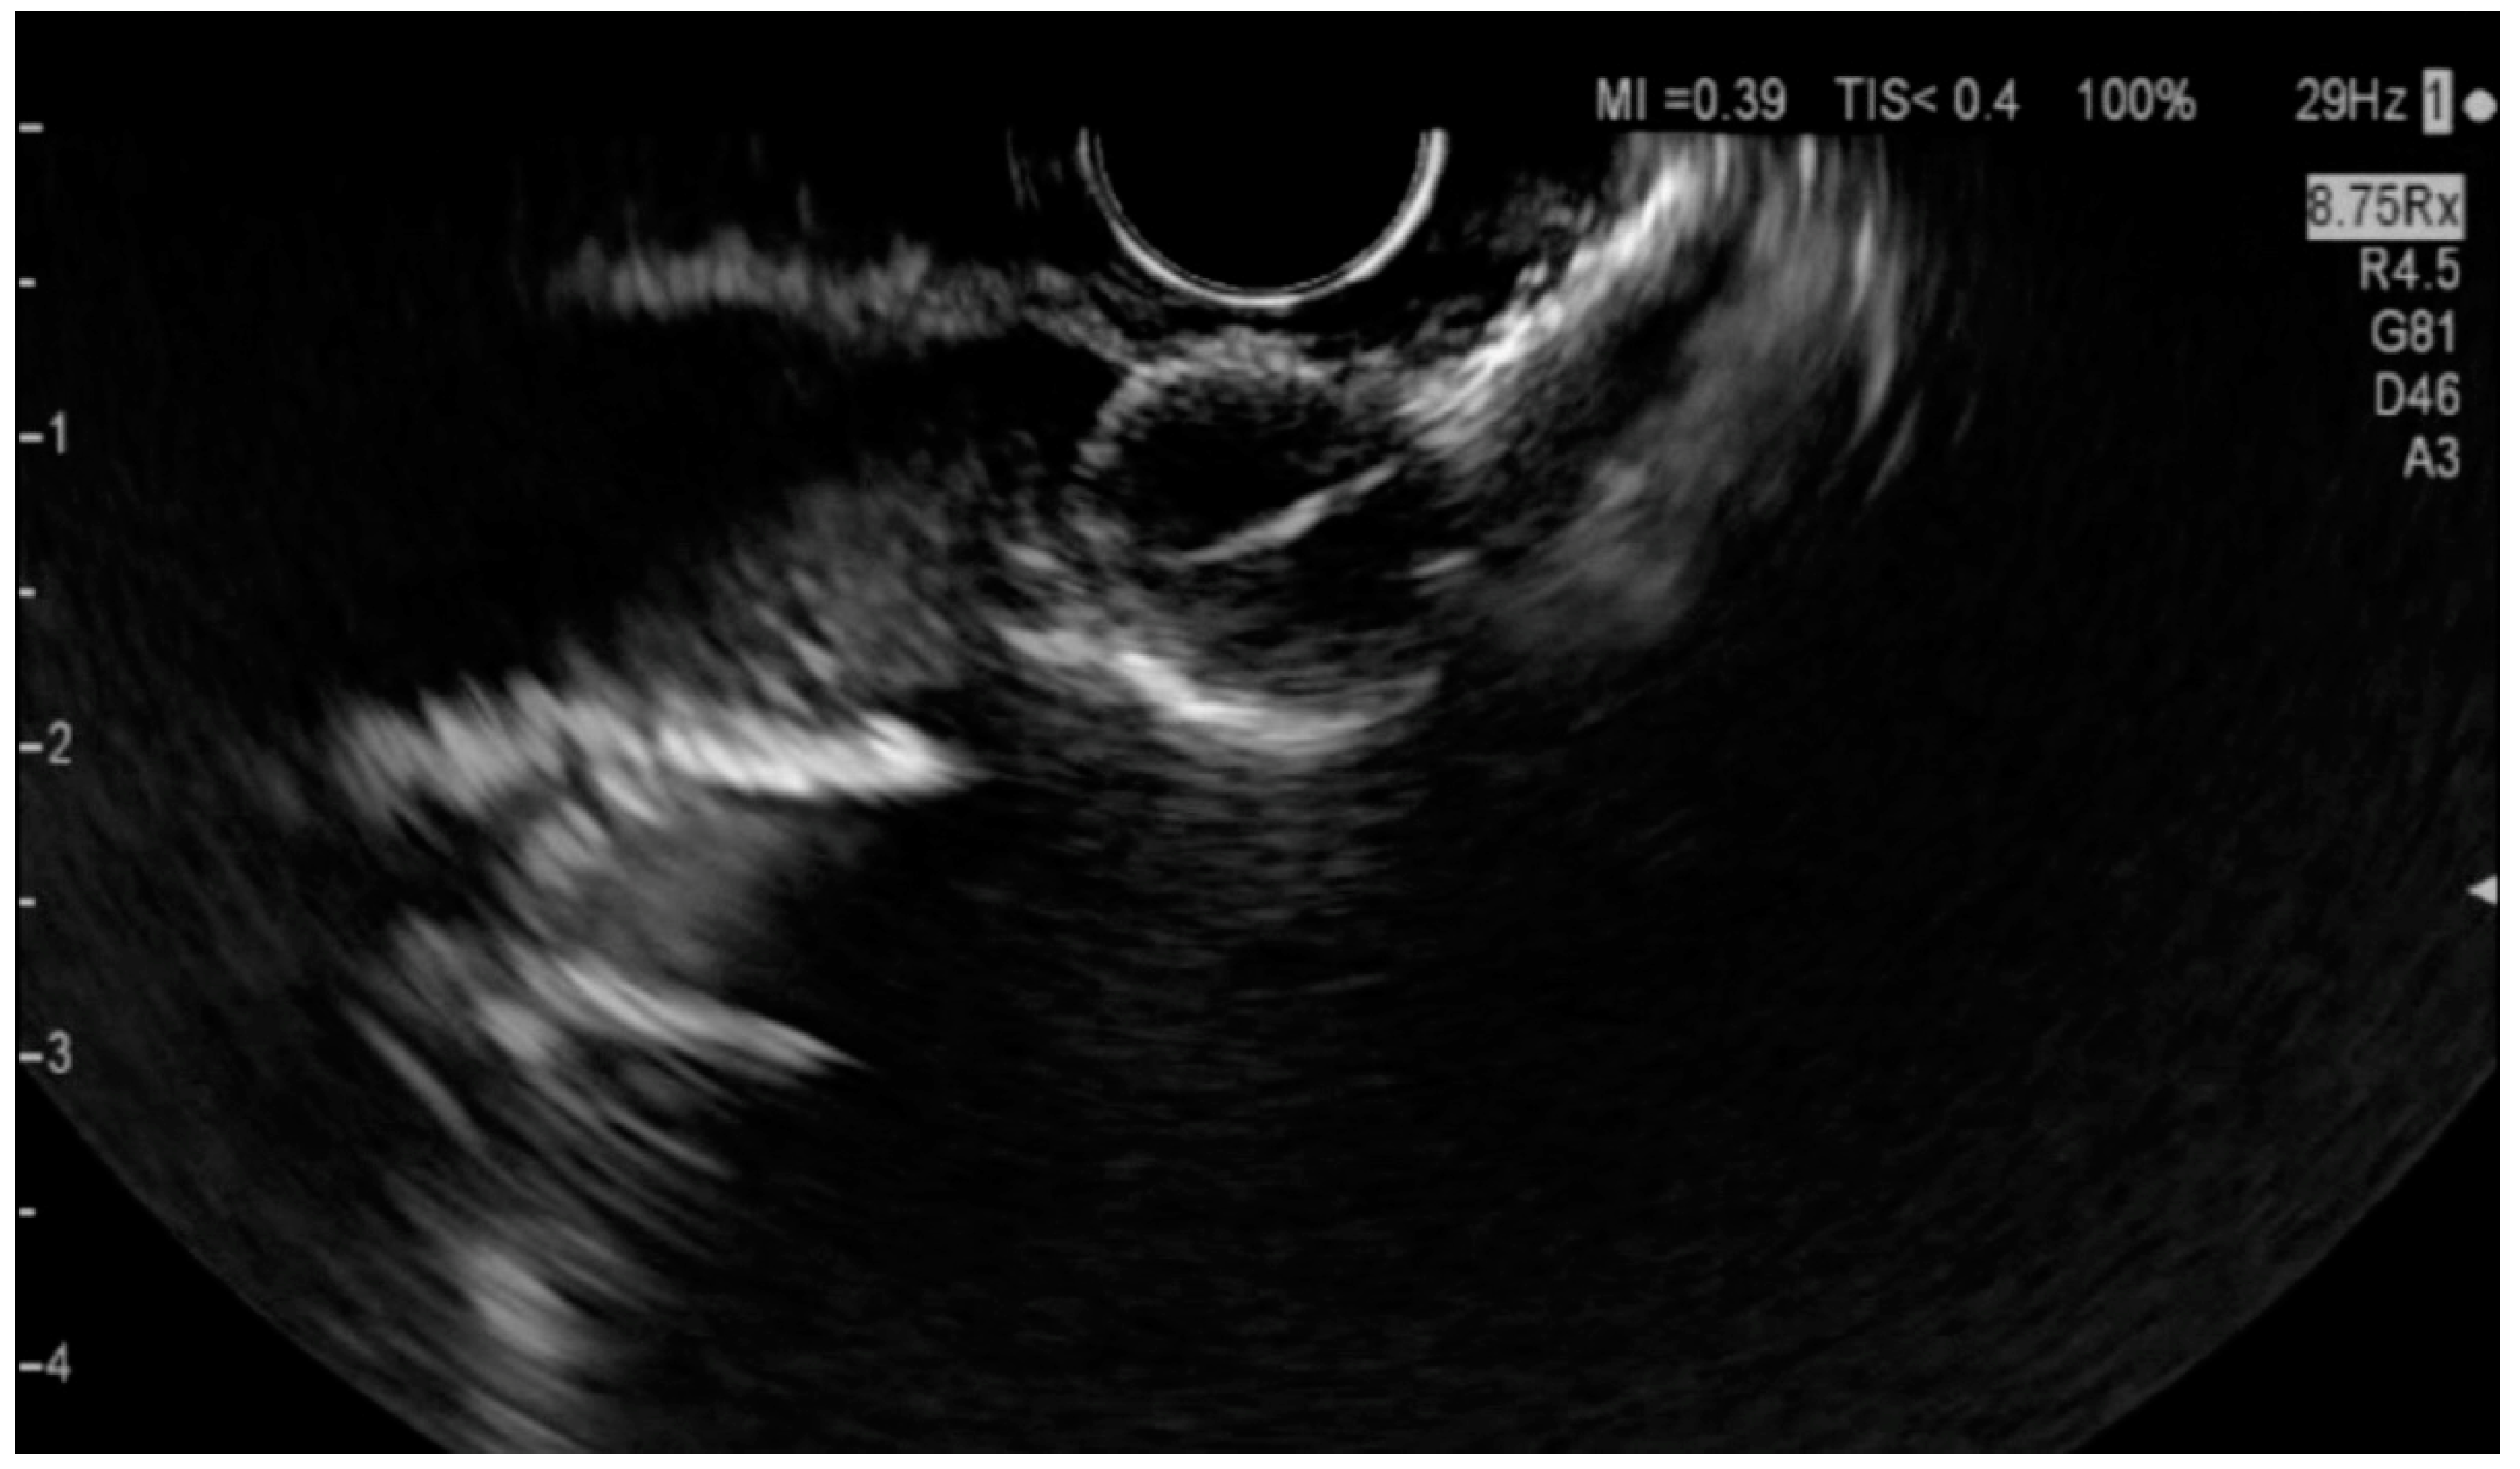

6.4.1. Endoscopic Ultrasound (EUS)

- Orzan, R.I.; Pojoga, C.; Agoston, R.; Seicean, R.; Seicean, A. Endoscopic Ultrasound in the Diagnosis of Extrahepatic Cholangiocarcinoma: What Do We Know in 2023? Diagnostics 2023, 13, 1023. [Google Scholar] [CrossRef] [PubMed]

- Otsuka, Y.; Kamata, K.; Hyodo, T.; Chikugo, T.; Hara, A.; Tanaka, H.; Yoshikawa, T.; Ishikawa, R.; Okamoto, A.; Yamazaki, T.; et al. Utility of contrast-enhanced harmonic endoscopic ultrasonography for T-staging of patients with extrahepatic bile duct cancer. Surg. Endosc. 2022, 36, 3254–3260. [Google Scholar] [CrossRef] [PubMed]